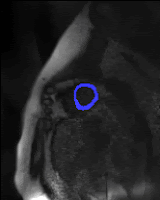

| ◉ Optimized Radial Sampling for Elimination of the Dark Rim Artifact in Myocardial Perfusion MRI

| Goal: This completed project aimed to develop a new scheme for minimizing subendocardial dark-rim image artifacts in cardiac perfusion MRI by optimizing the underlying point spread function (PSF) for radially sampled MRI to eliminate Gibbs ringing effects.